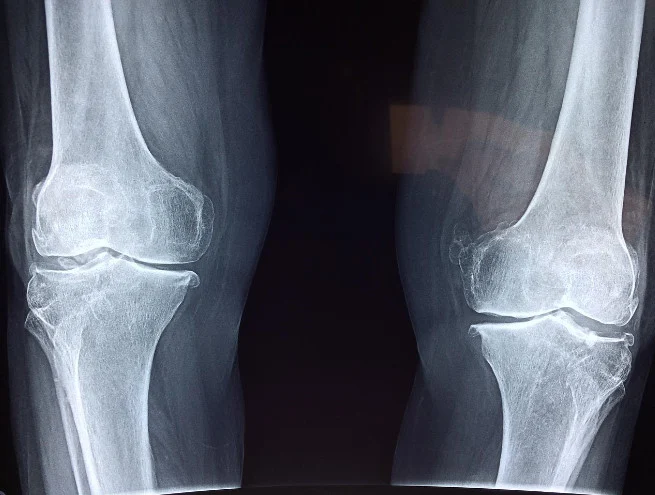

Na pierwszą wizytę zawsze warto zabrać ze sobą dokumentację medyczną. W większości przypadków ortopeda będzie wymagał zdjęcia RTG, na które skierowanie może wydać lekarz pierwszego kontaktu. Zależnie od zgłoszonego problemu, lekarz będzie badał ruchomość konkretnych stawów. Ortopeda stara się zlokalizować zniekształcenia czy nienaturalne ułożenie kończyn. Podczas wizyty lekarz może poprosić o wykonanie skłonów, przysiadów lub innych nieskomplikowanych ćwiczeń pozwalających ocenić zachowanie układu ruchowego. Poza badaniami RTG, ortopeda może zlecić również tomograf komputerowy czy rezonans magnetyczny.